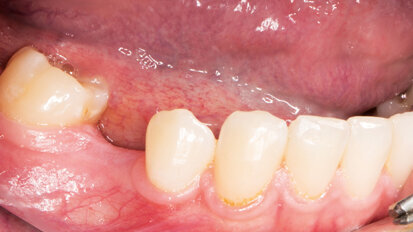

Rehabilitace Straumann

Po. 1. února 2021